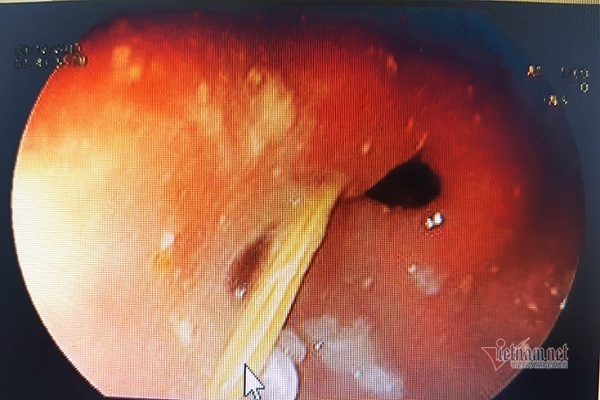

| Hình ảnh que tăm nhọn gây thủng dạ dày |

Sau khi thăm khám, các bác sĩ Khoa Thăm dò chức năng nội soi của bệnh viện đã nội soi và gắp thành công chiếc tăm tre nhọn 2 đầu, dài khoảng 2cm, đâm thủng dạ dày mà không gây biến chứng chảy máu cho nam thanh niên.

Theo các bác sĩ, chiếc tăm đã đâm xuyên hơn 1/3 vào thành dạ dày bệnh nhân A., nếu phát hiện muộn chiếc tăm có thể làm thủng ruột non và các tạng lân cận rất nguy hiểm.

Trong khi ngậm tăm tre, A. đã vô tình nuốt luôn que tăm nhọn 2 đầu, dài khoảng 2cm vào bụng.